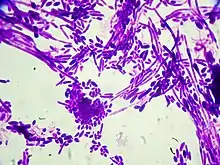

Gram stain of Candida dubliniensis cells (1000-fold magnification)

Candida dubliniensis is a fungal opportunistic pathogen originally isolated from AIDS patients. It is also occasionally isolated from immunocompetent individuals. It is of the genus Candida, very closely related to Candida albicans but forming a distinct phylogenetic cluster in DNA fingerprinting. It is most commonly isolated from oral cavities,[1] and is also occasionally found in other anatomical sites.